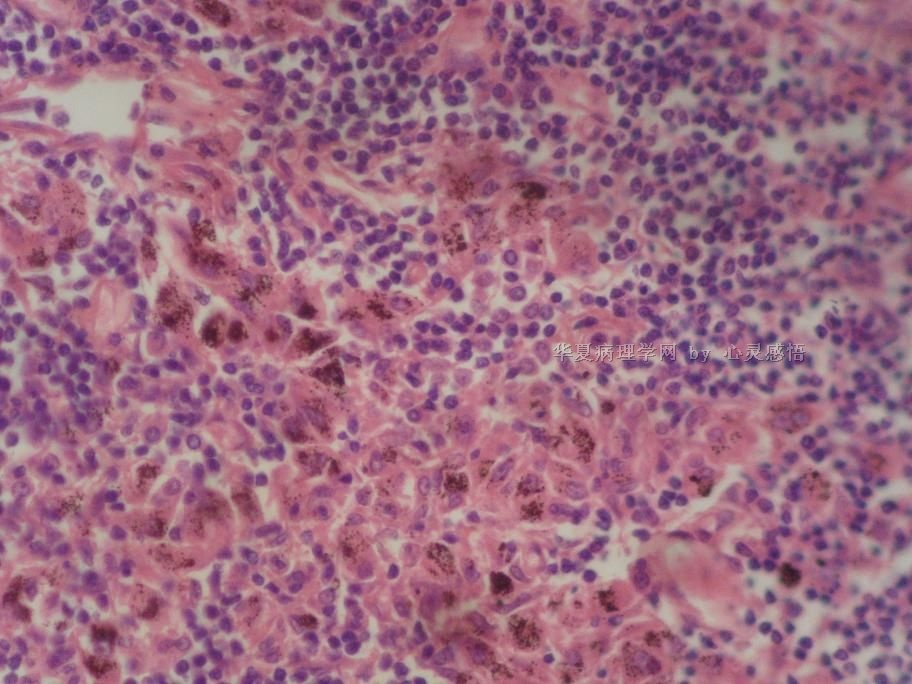

• 食道癌,淋巴结有没有转移,谢谢。图2

图2

1-6图是鳞癌。7-22图片无癌。

淋巴结没有转移

本帖最后由 于 2010-11-17 20:19:00 编辑  图14,19有转移

没有转移,食道旁的淋巴结和肺旁的淋巴结相似,含有吞噬细胞。